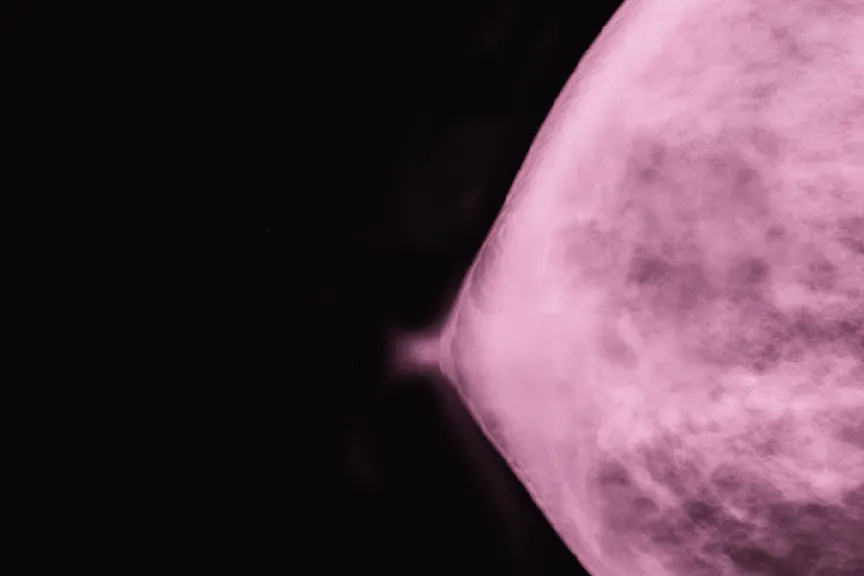

虽然大多数这些乳头问题可能没有大不了的事,但如果他们坚持不懈,他们可以是潜在问题的迹象。据怀疑,看到你的文件 - 我们毕竟谈论你的乳房。“特别是如果这些变化在几天或几周内迅速变得更糟,或者给出的抗生素和其他医疗似乎并没有改善,那么你可能想要求乳腺癌评估,”她说。这可能包括乳房X光检查以及其他筛选。